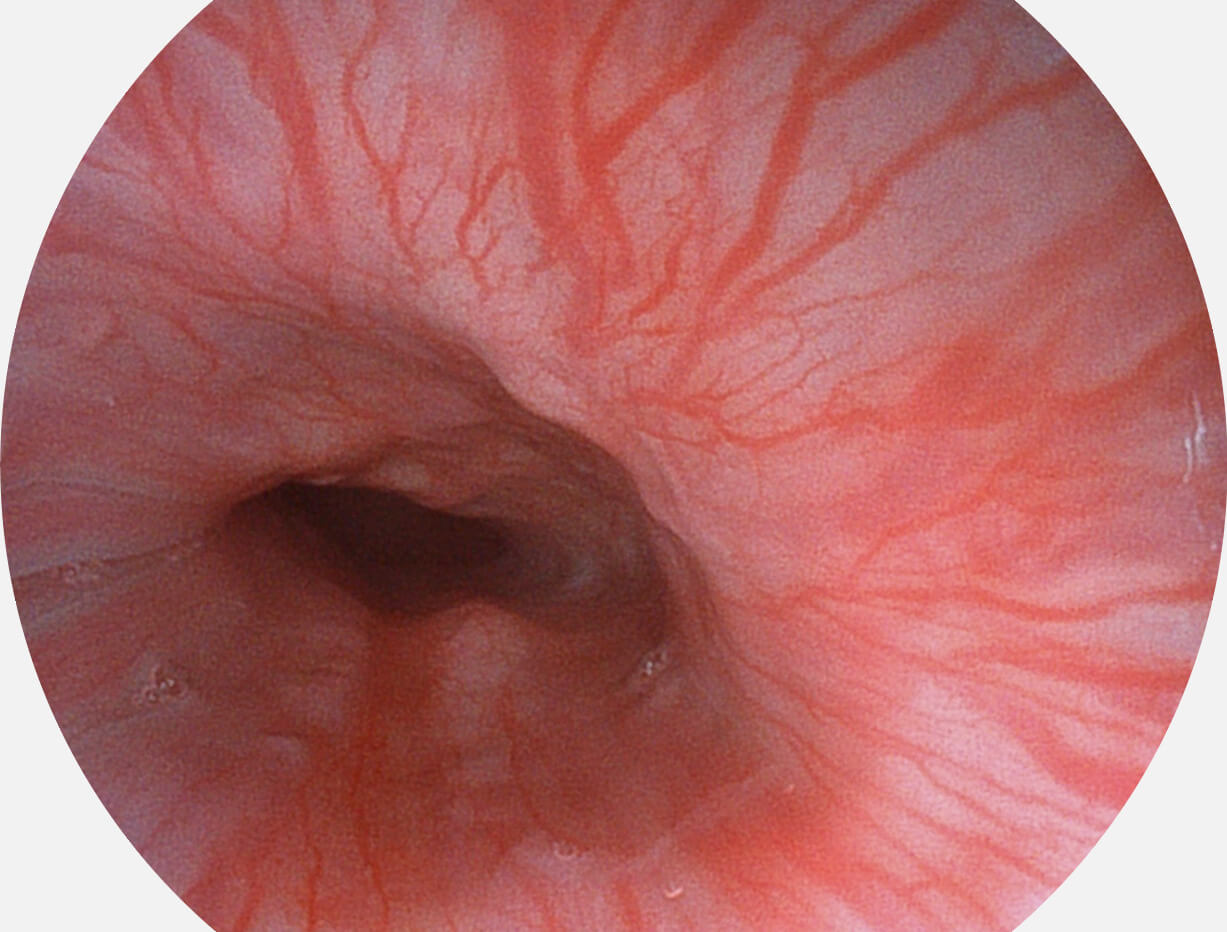

白光图像

VIST图像

强调浅层黏膜结构的同时,保证照明亮度和提升浅层微血管与中层血管颜色对比度,病变边界更清晰。

采用光路合束技术,光谱自由度高,实现了更丰富的照明模式,染色模式SFI及VIST,从远景到近景,助力消化道早期疾病诊断。